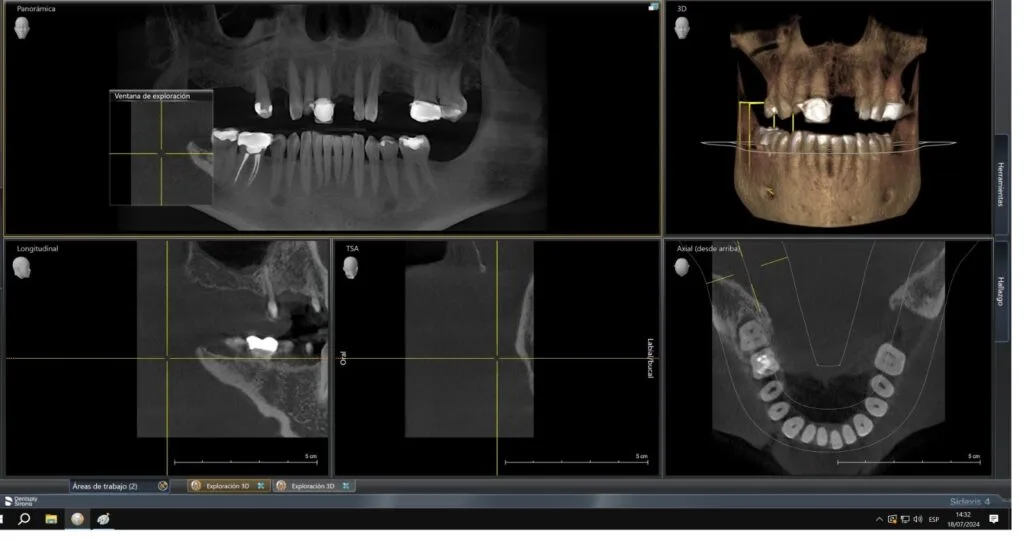

Este paciente presenta la pérdida de cinco piezas dentales y cuenta con un hueso maxilar en óptimas condiciones para la colocación de implantes dentales.

Nuestra consulta es muy detallada; te explicamos cada paso del tratamiento utilizando tus propias imágenes para una mejor comprensión.

Nuestra tecnología de vanguardia, como la tomografía 3D y la planificación virtual de implantes, asegura que el implante se coloque en la posición más adecuada para tu anatomía bucal.

La tomografía 3D es una herramienta clave en las consultas iniciales, ya que nos permite obtener una imagen precisa de tu estructura ósea y planificar el tratamiento con exactitud. Esto no solo mejora la precisión del procedimiento, sino que también reduce los riesgos y aumenta las probabilidades de éxito.